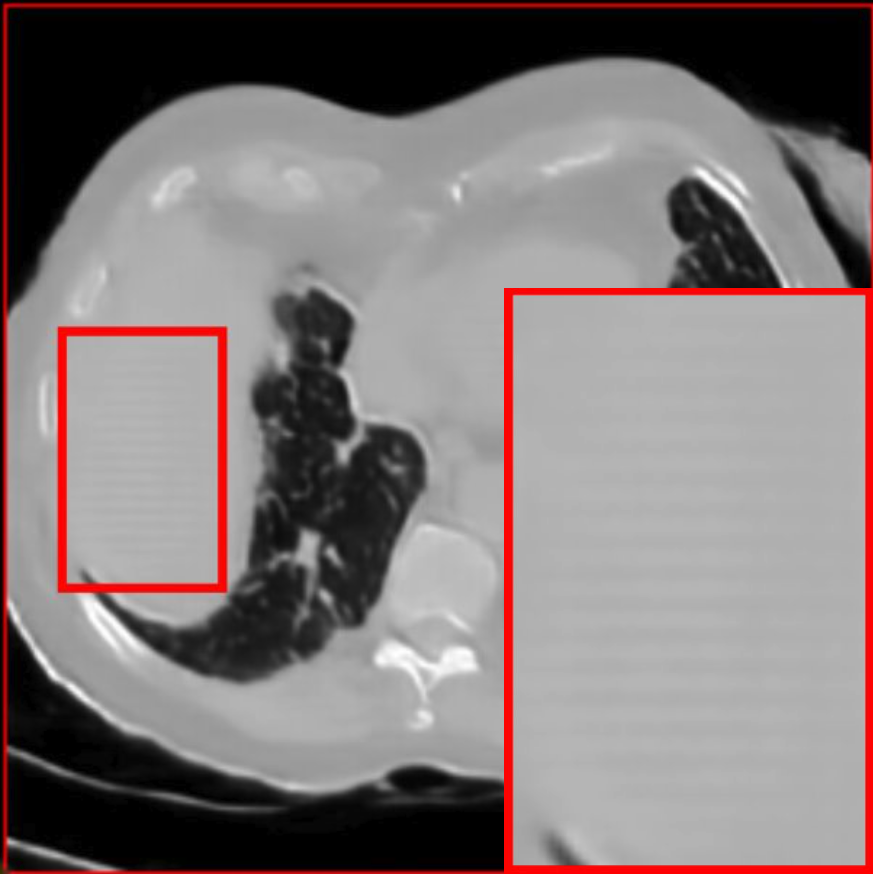

Figure 2: Qualitative comparison across axial (top row), sagittal (middle row), and coronal (bottom row) views. Columns correspond to different methods. MAISI-DDPM and MAISI-v2 in this figure are unconditional synthesis which do not use ControlNet or segmentation maps.

Qualitative Evaluation:

Figure 2 presents representative slices from the axial, sagittal, and coronal planes. GenerateCT (Hamamci et al. 2024) is a 2D model, so it lacks inter-slice consistency, leading to poor image quality in the sagittal and coronal views. MedSyn (Xu et al. 2024) produces noticeably blurry results with mosaic-like artifacts, such as region inside the red box. HA-GAN (Sun et al. 2022) generates visually sharp images but with mosaic-like artifacts, such as region inside the red box. Also, its voxel spacing is not available, which limits its applicability in real-world medical imaging tasks. Moreover, all three methods are restricted to synthesizing small anatomical regions. In contrast, both MAISI and MAISI-v2 are capable of generating high-quality 3D volumes that span larger body regions while preserving fine anatomical details and realistic structure.